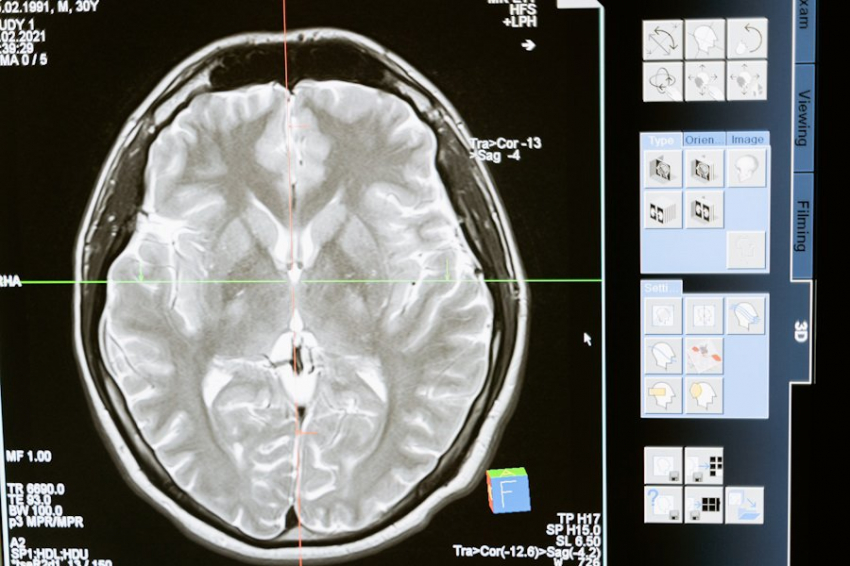

Фото из открытых источников Медики и научные специалисты давно пытаются выяснить, почему мужчины и женщины по-своему ведут себя при психиатрических и неврологических патологиях. Американскими учёными из нью-йоркской Медицинской школы имени Гроссмана с помощью искусственного интеллекта (ИИ) выявлены различия в мозге мужчин и женщин. Как сообщает журнал Scientific Reports, эксперты подвергли обработке с помощью нейросети солидный массив данных МРТ разных людей. Который позволил сделать выводы о